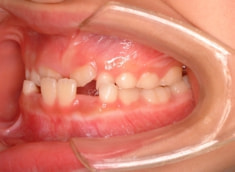

治療前

小児期ケース:反対咬合(受け口)

治療法:上顎拡大装置+フルパッシブブラケット(クリアスナップ)+フェイスマスク等

治療期間:1年3ヶ月

解説:上顎の急速拡大により、骨格的に拡大、前方牽引を促します。